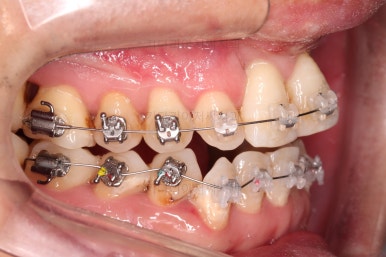

1. 초진 시 입안의 모습

부산구순구개열교정 키다리아저씨치과에 처음 내원하셨을 당시의 입안의 모습입니다.

이번 환자분도 이와 같은 일반적인 특징이 그대로 나타나 있었습니다.

양측성 구순구개열이었으므로 작은 앞니(대문니와 송곳니 사이)가 양쪽 다 결손이었고, 또 다른 이유로 아래 앞니도 1개 없는 상태였습니다.

위아래 장치를 부착했습니다.

초기 단계의 주안점은 아랫니와 악궁과 어울리는 윗니 악궁의 형태를 만들어 주는 것이고요.

악궁확장장치를 사용하지 않은만큼 철사의 형태를 잘 잡아가면서 악궁 형태를 개선시킵니다.

교정 10개월째인데, 악궁형태 많이 좋아졌고, 가지런한 느낌도 많이 좋아졌습니다.